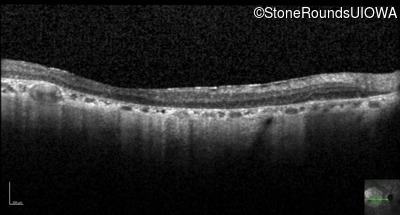

Optical Coherence Tomography - Right - 20/160 +2 sc

Exemplar / OCT Stack